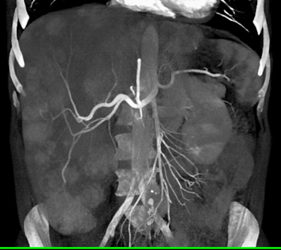

Metastatic Carcinoid Tumor